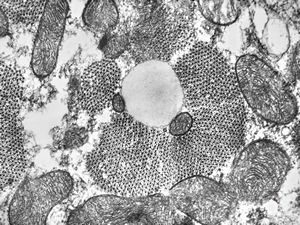

M, | newborn heart … mitochondrial cardiomyopathy … autopsy sample

M, | newborn heart … mitochondrial cardiomyopathy … reduced mitochondrial cristae … autopsy sample